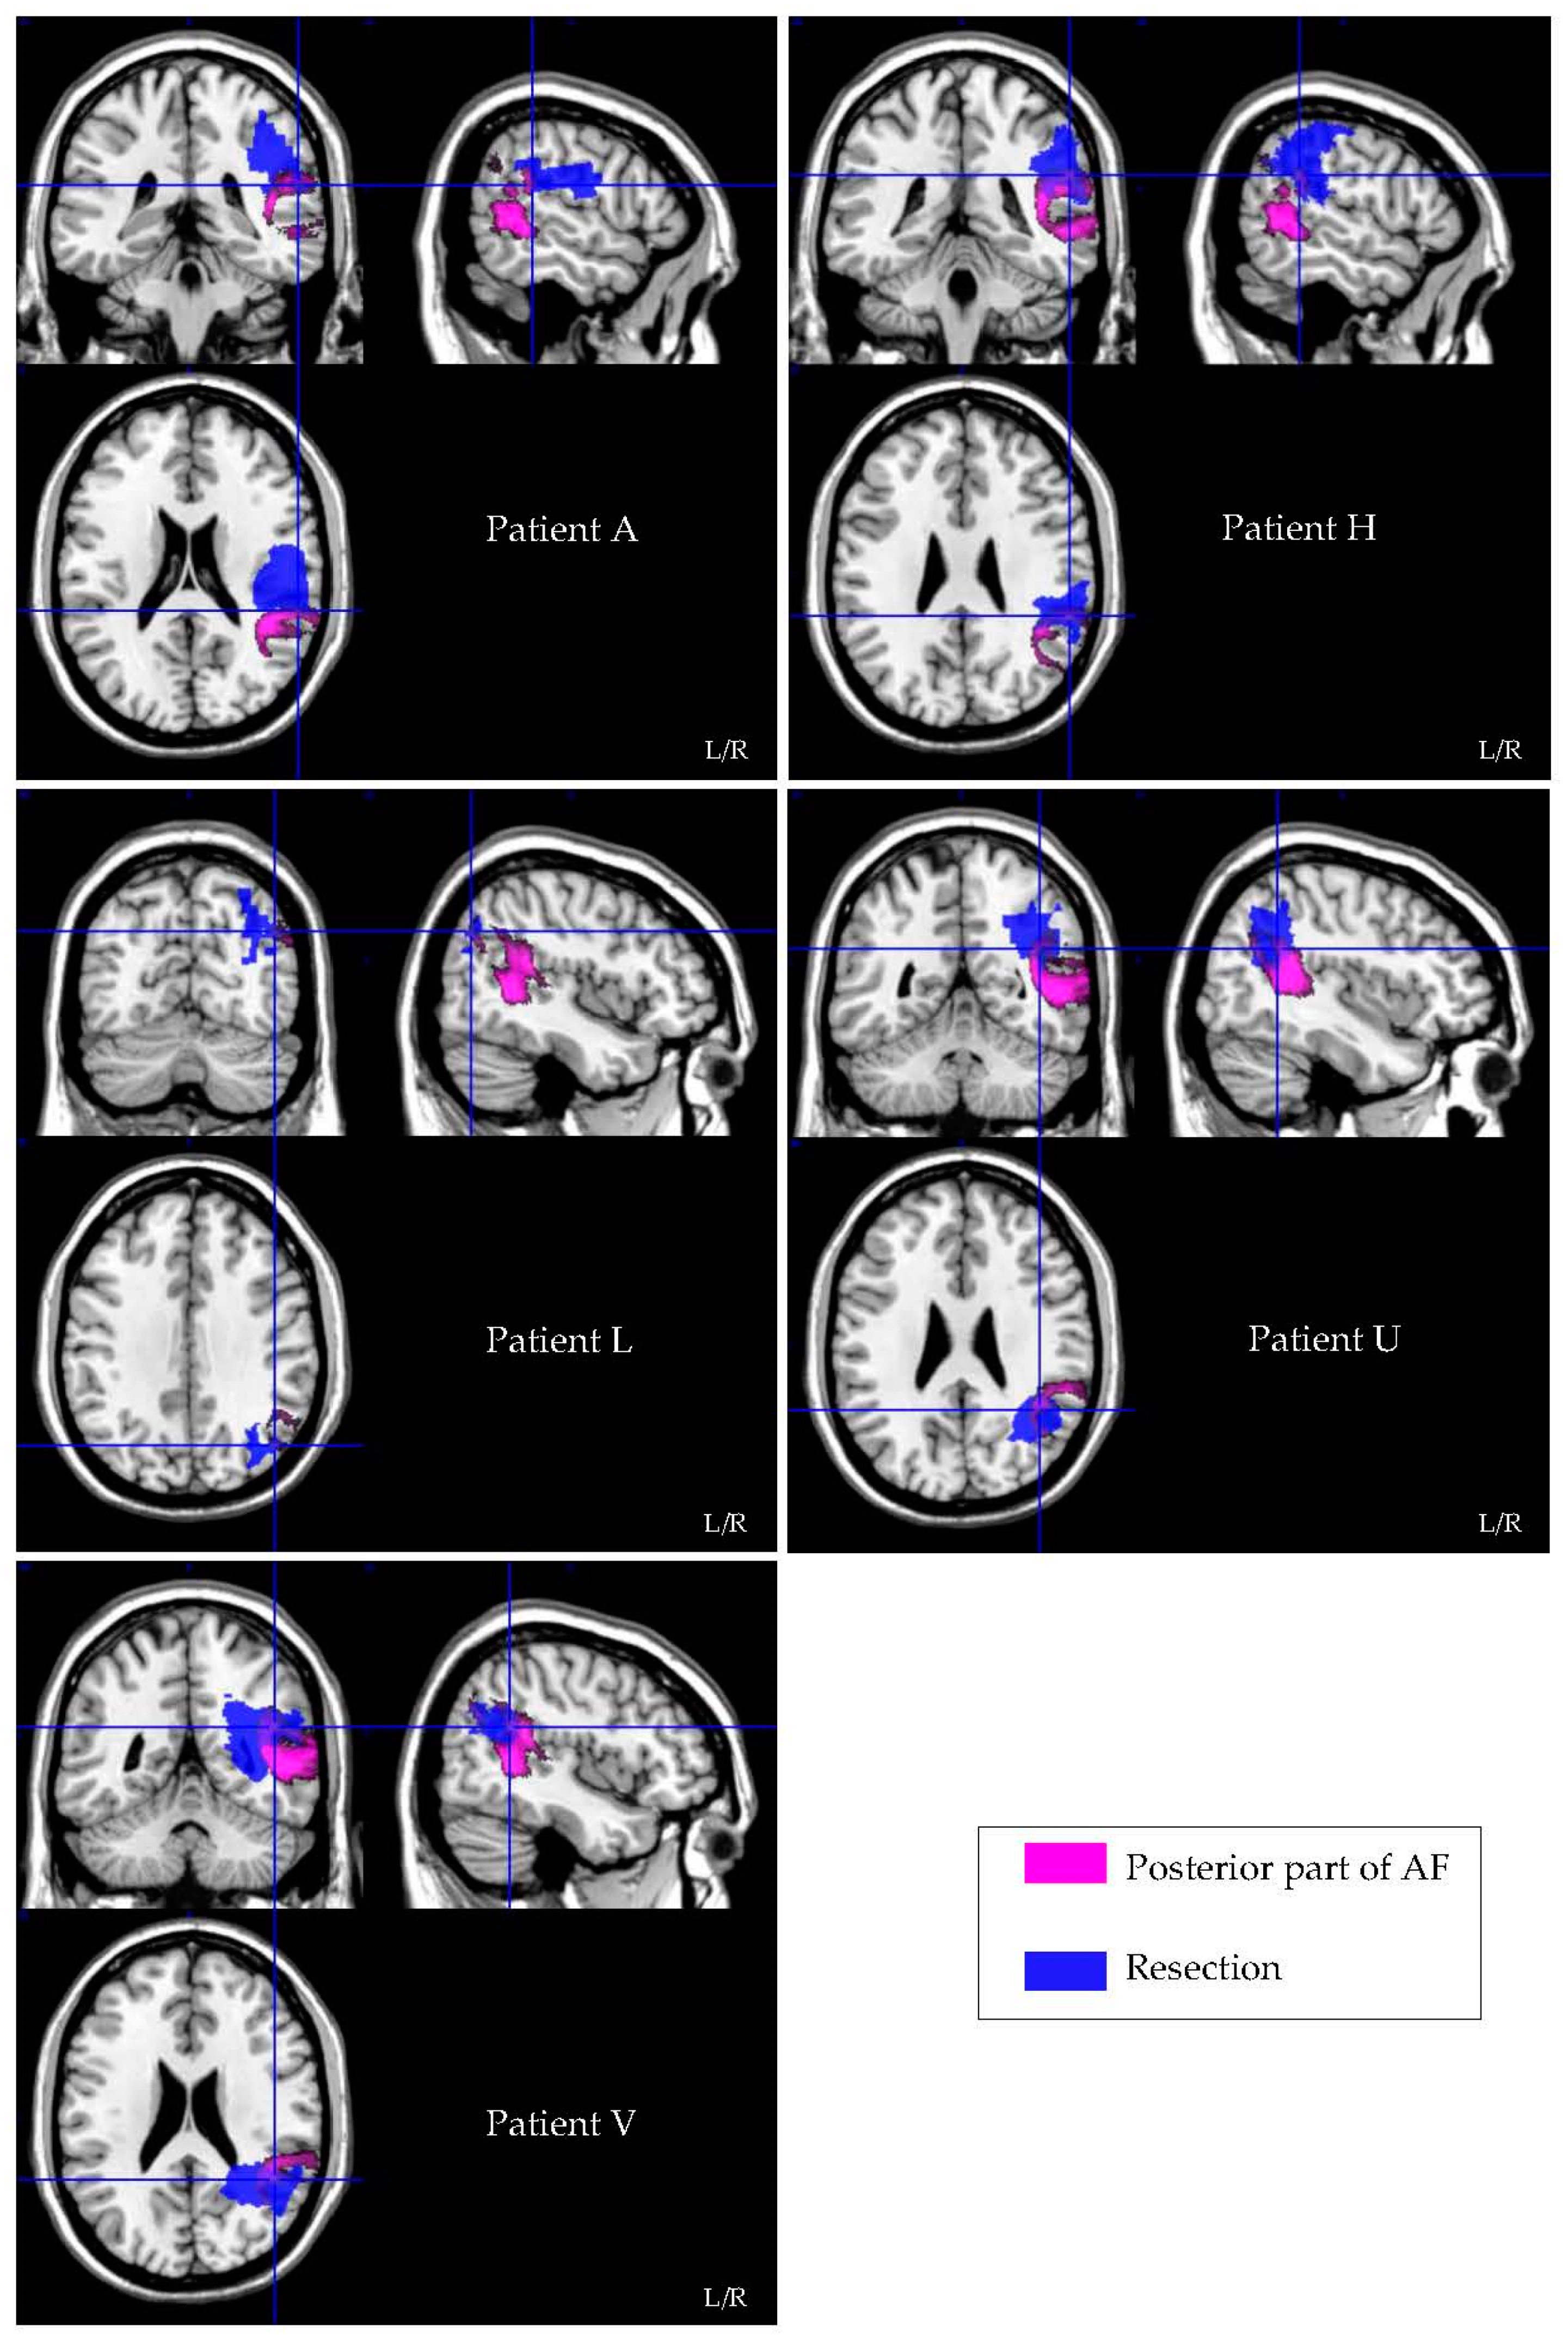

3.4. Resection Volume Measurements